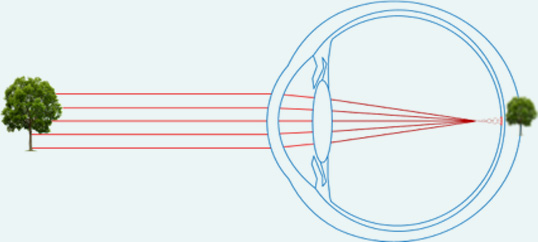

La myopie est le trouble affectant la netteté de la vision de loin. Elle se manifeste chez le sujet dont l'oeil est trop long par rapport à sa puissance. Les rayons lumineux provenant d'un objet lointain vont alors converger en avant de la rétine, sur laquelle l'image formée sera floue !